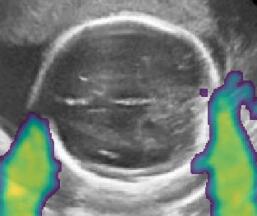

Fig. 6 compares the shadow confidence maps of the state-of-the-art methods and the proposed methods. RW and have the same parameters as used for Table I. The shadow confidence maps of the baseline, the proposed method and the proposedAG method are generated directly from input shadow images by confidence estimation networks. Overall, the proposed method and the proposedAG method achieve more visually reasonable shadow confidence estimation than the baseline and the state-of-the-art on different anatomical structures shown in Fig. 6. The proposed method and the proposedAG method are able to highlight multiple shadow regions while the RW algorithm shows limitations for most cases, especially for disjoint shadow regions.

Row I in Fig. 6 shows a fetal brain image from . The confidence estimation of shadow regions from the baseline, the proposed method and the proposedAG method are similarly accurate since we use fetal brain images to train the confidence estimation networks in these three methods. These outperform [16] and [22]. Rows (II-IV) in Fig. 6 show shadow confidence maps of non-brain anatomy from , including lips, abdominal and cardiac. The baseline failed on unseen data during inference. However, the proposed methods are able to generate accurate shadow confidence maps because of the generalized shadow features obtained by the shadow-seg module. Furthermore, the “Lips” example shows that our method is capable of detecting weaker shadow regions that have not been annotated in manual segmentation. This indicates that the confidence estimation network has learned general properties of shadow regions.